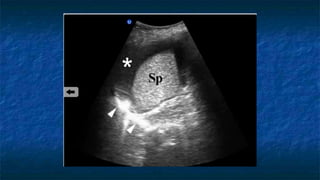

4)FAST: LUQ exam

 Evaluating

 Spleno-renal interface

 Possibility of fluid in splenorenal recess

and presplenic /subphrenic space( most

common space for fluid collection in

LUQ)

FF

Kidney

Spleen

Diaphragm

4)FAST: LUQ exam Probe placed  Perpendicular  Mid - coronal plane  Just superior to the iliac crest  Probe facing  Towards patient’s head  Evaluating  Spleno-renal interface  Possibility of fluid in splenorenal recess and presplenic /subphrenic space( most common space for fluid collection in LUQ)